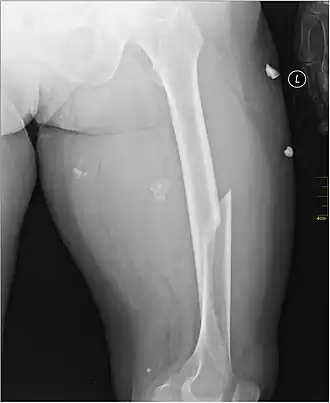

X-ray image of a femoral shaft fracture